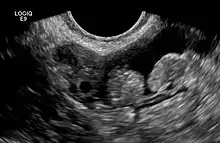

2 epiploic appendages next to an ovary in pelvic ultrasound

The epiploic appendices (or appendices epiploicae, or epiploic appendages, or appendix epiploica, or omental appendices) are small pouches of the peritoneum filled with fat and situated along the colon, but are absent in the rectum.

They are chiefly appended to the transverse and sigmoid parts of the colon, however, their function is unknown.

The appendages can become inflamed in a painful process known as epiploic appendagitis which can mimic acute appendicitis and other conditions.